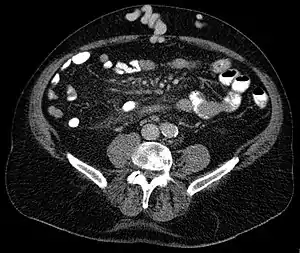

| Axial CT showing portosystemic collateral circulation via the umbilical vein: caput medusae in liver cirrhosis | |

Caput medusae (Cirsomphalos[1]) is the appearance of distended and engorged superficial epigastric veins, which are seen radiating from the umbilicus across the abdomen. The name caput medusae (Latin for "head of Medusa") originates from the apparent similarity to Medusa's head, which had venomous snakes in place of hair. It is also a sign of portal hypertension.[2] It is caused by dilation of the paraumbilical veins, which carry oxygenated blood from mother to fetus in utero and normally close within one week of birth, becoming re-canalised due to portal hypertension caused by liver failure.